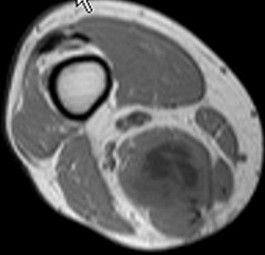

A 15-year-old male presents with deep knee pain awakening him at night. Radiographs show a permeative destructive lesion in the distal femoral metaphysis with a 'sunburst' periosteal reaction and Codman's triangle.

Biopsy confirms high-grade conventional osteosarcoma. What is the most critical prognostic factor for long-term overall survival in this patient?

Explanation

For localized high-grade osteosarcoma, the most important prognostic indicator is the histologic response to neoadjuvant chemotherapy. This is evaluated during the definitive resection. A 'good response' is typically defined as greater than 90% or 99% tumor necrosis. Patients who achieve this level of necrosis have a significantly improved disease-free and overall survival rate compared to 'poor responders' who have extensive viable tumor cells remaining.